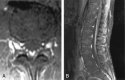

F<sc>ig</sc> 9.

Fig 9.

Subtle thoracic cord signal abnormalities in a patient with moderate-to-severe neurologic deficits. A, Sagittal T2WI demonstrates increased signal intensity in the mid-to-lower portion of the central thoracic cord. B, Sagittal contrast-enhanced T1WI demonstrates patchy areas of subtle enhancement.